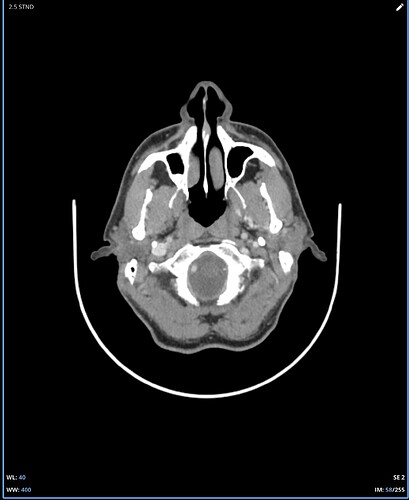

I’m not good at tech so can’t do labels or arrows for your imaging, but on the first two images, there’s clear compression of the IJV between the styloid process & the C1 process. In the first one, it’s not clear whether it’s just the imaging or whether there’s also narrowing of the IJV further down- it disappears so that could be compression but can’t see clearly, if it was compressed there it would indicate TOS which might explain some of your arm symptoms…

In the other two CT images, you can see the styloids really clearly- they’re quite elongated, pretty thick right at the top, and both sides look close to the C1 processes, which is a common place for the IJVs to get compressed.

Where I am in Canada and the healthcare system is slow, I travelled to a different province in November for an updated CT. The report did note a pretty severely squished left jugular between C1 and the styloid and some compression on the right side as well so at least it is acknowledged on a report now. It sure looks like C1 is causing a problem even moreso than the styloid but I am not in a position to figure this out. I can’t help but wonder if I was born this way and it’s actually not the problem at all. Anyway, I would appreciate any feedback whatsoever on these new images….is a C1 shave a must do? I hope this isn’t too many images to post, I was trying to show the full picture of how the compression looks. It is very difficult to pick out the left jugular because it becomes so small:

It’s clear that your right IJV is dominant based on its size vs the left one. I’ve annotated a couple of your 3D images to show what I see & will comment below them. Scrolling through your axial images, it’s obvious you have significant bilateral IJV compression.